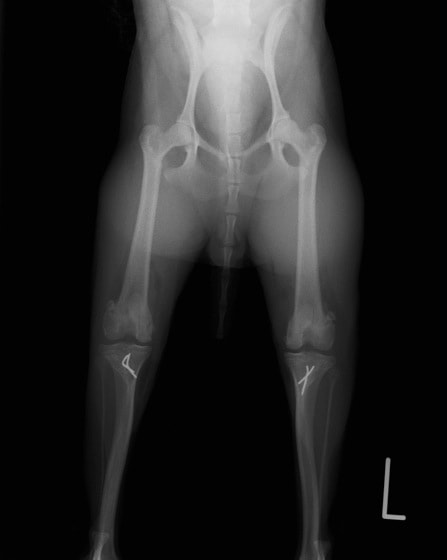

■ 症例22 ポメラニアン 1歳5か月 去勢雄

左後肢の挙上を主訴に来院した。整形学的検査、レントゲン検査より左右の膝蓋骨脱臼(左GradeⅡ〜Ⅲ、右Grade Ⅱ)を認めた。また、脛骨の前方引き出し試験の際に、引き出し兆候は認められないものの、疼痛が認められたため、前十字靭帯の損傷が疑われた。術中における、目視および関節内の操作によって、前十字靭帯の損傷や過伸展といった異常が認められなかったため、膝蓋骨脱臼の整復のみ実施した。手術手技は縫工筋及び内側広筋の解放、脛骨粗面の外側転位、滑車ブロック形造溝術、内外側関節包の縫縮を実施した。本症例は跛行もなく経過良好である。しかし、頸骨高平部の角度(TPA)が 右26.2°、左24.9°であり、解剖学的に前十字靭帯損傷のリスクが高いことから今後の経過に注意が必要である。